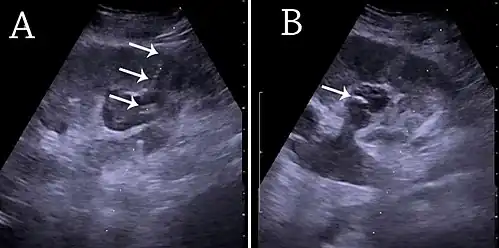

Вмешательство выполняется под УЗ- и рентген-контролем в условиях рентген-операционной.[2] Данный метод дренирования предпочтителен у пациентов онкологического профиля, при технической невозможности установки внутреннего мочеточникового стента, а также в некоторых экстренных случаях. В силу того, что вмешательство проводится через паренхиму почки, необходимо предварительное обследование с целью исключения нарушения свертывающей системы крови ввиду риска кровотечения. В случае планового дренирования почки путем нефростомии состояние больного, как правило, позволяет выписку на следующий день.

- После обезболивания в кожу поясничной области, под контролем рентгена и ультразвука, вводится игла.

- После проникновения иглы в почечную лоханку, через нее вводится контрастное вещество, позволяющее оценить точность введения и внутреннее строение почки.